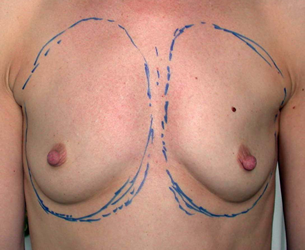

L’augmentation mammaire par pose d’implants est la seule alternative pour augmenter significativement et harmonieusement la taille des seins.

Les patientes de cet album ont des voies d’abord différentes, comme des tailles de prothèses ou de positionnement par rapport au muscle pectoral.